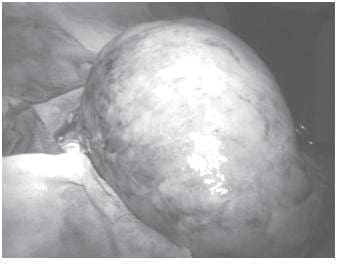

El paciente se sometió a cirugía, previa transfusión sanguínea, bajo anestesia general. A través de una incisión media supraumbilical e infraumbilical, se encontró una gran masa tumoral que comprometía el ángulo esplénico del colon y una masa tumoral redondeada y fija en la bifurcación de los vasos ilíacos derechos. Se resecaron ambas tumoraciones y se restableció el tránsito intestinal con anastomosis término-terminal de colon, en un plano de sutura (figuras 3 y 4).

FIGURA 3. Tumor de Burkitt que compromete el ángulo esplénico del colon